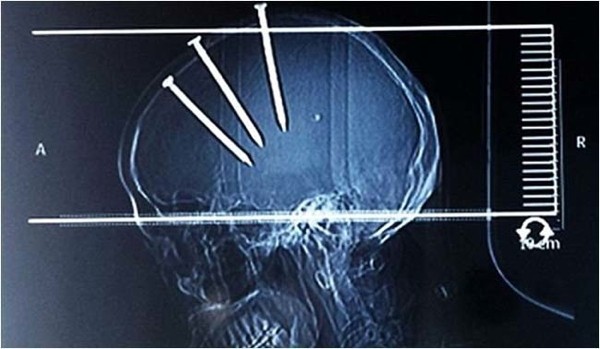

Çivilerin başları açıkça dışarıdan bile görünürken doktorlar Çinli adamın röntgenini çekti ve 3 koca çivi ile karşılaştı.